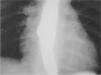

Entre las pruebas complementarias realizadas el electrocardiograma, hemograma y bioquímica no presentaban alteraciones. En la radiografía de tórax se observaba una masa de contornos lobulados, bien delimitada en mediastino superior que originaba ensanchamiento bilateral; en la tomografía computarizada (TC) torácica con contraste (fig. 2) se visualizaba una masa de densidad agua, sin verse adenopatías, la lesión se consideró compatible con quiste de duplicación. En el parénquima pulmonar se observaba una hiperaireación del lóbulo medio con imágenes quísticas alternando con parénquima normal que podría corresponder a malformación adenomatoidea quística o enfisema lobular congénito (fig. 3). El tránsito digestivo superior mostraba una compresión en el tercio inferior de esófago por una masa paratraqueal derecha y en la esofagoscopia no se vio comunicación con la luz esofágica.

Figura 2.TC torácica con contraste: masa de densidad agua, no se ven adenopatías, lesión compatible con quiste de duplicación.